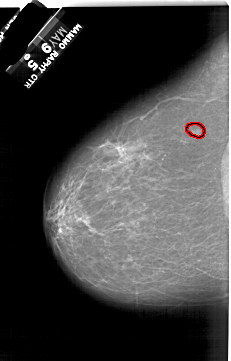

A_1164_1.LEFT_MLO

LEFT_MLO LINES 6586 PIXELS_PER_LINE 4111 BITS_PER_PIXEL 12 RESOLUTION 43.5 OVERLAY

FILE: A_1164_1.LEFT_MLO.OVERLAY

TOTAL_ABNORMALITIES 1

ABNORMALITY 1

LESION_TYPE MASS SHAPE IRREGULAR MARGINS ILL_DEFINED

ASSESSMENT 4

SUBTLETY 4

PATHOLOGY MALIGNANT

TOTAL_OUTLINES 1

BOUNDARY